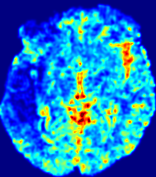

Figure 4: PIANO feature maps for another patient in the ISLES 2017 training set, where the lesion is located in the right hemisphere. Top row: segmented stroke lesion region (white) on different slices. The corresponding slices for the PIANO feature maps are shown in the following rows.

For a better insight into an estimated velocity field 𝐕𝐕{\bf{V}} and diffusion field 𝐃𝐃{\bf{D}}, we compute the following maps: (1) 𝐕rgbsubscript𝐕𝑟𝑔𝑏{\bf{V}}_{rgb}: Color-coded orientation map of 𝐕=(Vx,Vy,Vz)T𝐕superscriptsuperscript𝑉𝑥superscript𝑉𝑦superscript𝑉𝑧𝑇{\bf{V}}=(V^{x},V^{y},V^{z})^{T}, obtained by normalizing 𝐕𝐕{\bf{V}} to unit length and mapping its 3 components to red, green, blue respectively; (2) 𝐕2subscriptnorm𝐕2\|{\bf{V}}\|_{2}: 222 norm of 𝐕𝐕{\bf{V}}; (3) D𝐷D: scalar field in Eq. 5.

Fig. 3 and Fig. 4 show the PIANO feature maps estimated from two ISLES 2017 patients: all are highly consistent with the lesion in both cases. Details of the blood flow trajectories are revealed in 𝐕rgbsubscript𝐕𝑟𝑔𝑏{\bf{V}}_{rgb} by the ridged patterns and the sharp changes of colors in the unaffected (right) hemisphere, while the flat patterns appearing within the lesion provide little directional information about the velocity and indicate low velocity magnitudes. Velocity magnitudes are more directly visualized via 𝐕2subscriptnorm𝐕2\|{\bf{V}}\|_{2}, from which one can easily locate the lesion where 𝐕2subscriptnorm𝐕2\|{\bf{V}}\|_{2} is low. D𝐷D also indicates lower diffusion values in the lesion, though with less contrast potentially due to the fact that it captures the accumulated effect of CA diffusion at the voxel-level.